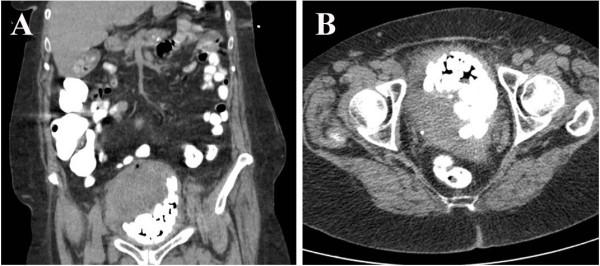

A 76-year-old Caucasian woman presented to the emergency department with gross hematuria and dysuria for one month. Urinalysis showed many RBCs and WBCs with positive nitrite. She was admitted with an initial impression of urinary tract infection and intravenous ceftriaxone was started. Urine culture grew greater than 100,000 cfu/ml of Enterococcus species. Computed tomographic imaging of the abdomen/pelvis with oral contrast revealed a markedly distended bladder with hemorrhage, multiple calculi, and diffuse bladder wall thickening. Cystoscopy was performed for diffuse bladder wall thickening and demonstrated numerous bladder stones, a bladder mass, and organized blood clots. Biopsy of the mass was consistent with high-grade carcinoma with squamous differentiation. The bladder cancer was not surgically resectable and radical cystectomy was not recommended due to old age and poor functional status. The patient refused chemotherapy and she died in 6 months.